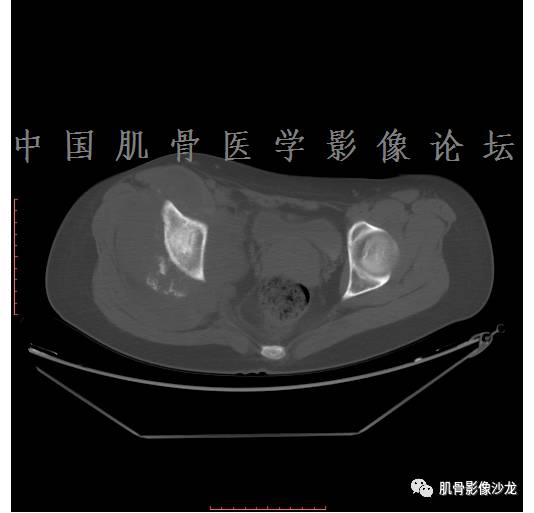

患者于2月前无明显诱因下出现腰骶部疼痛,夜间为重,逐渐加重伴左下肢麻木、疼痛,并有行走活动受限,在我院就诊,摄腰椎及骶髂部CT提示:腰椎骨质退变,腰3-4、4-5椎间盘膨出,骶髂关节炎。自用非甾体抗炎药无好转,再次来院就诊,门诊拟“骶髂关节炎”收住我科。病程无间歇性跛行,大小便正常。

专科检查:神清,脊柱无侧弯后凸畸形,椎体各节段无压、叩痛,双侧棘突旁无压痛,双侧骶髂关节压痛明显,左下肢放射痛,浅感觉较健侧减退,腰椎前屈后伸活动受限,膝、跟腱反射正常。

辅助检查:腰椎及骶髂部CT提示:腰椎骨质退变,腰3-4、4-5椎间盘膨出,骶髂关节炎。

雪舞 :第二例,位于骶骨,有骨质破坏并有软组织肿块,软组织肿块边界清

雪舞: 第二例我们能够看到破坏与软组织肿块不成比例,软组织肿块大,破坏小

雪舞 :第二例挺难的,骨质破坏是溶骨性的,局部皮质中断,软组织肿块外缘光滑